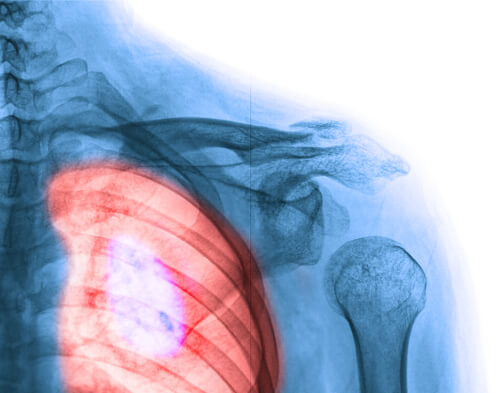

1. Рак на гърдата

Ракът на гърдата има без съмнение най-голямо разпространение при жените. Въпреки това, трябва да споменем нещо важно тук: той има и най-висок процент на оживели пациенти.

Вероятно познавате някой в социалния ви кръг, който има рак на гърдата или може би дори сте загубили любим човек поради тази ужасна болест. Но тъй като науката напредва с всеки изминал ден, все повече и повече жени оцеляват. Прегледи на гърдите, които можете да правите сами вкъщи, и мамографиите са ключови фактори в ранното откриване. Ето няколко признаци и симптоми, които трябва да имате предвид: